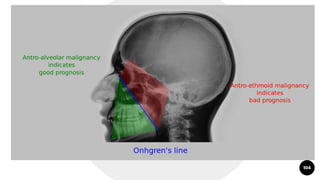

Squamous Cell Carcinoma

103

Radiopaque

Destruction of walls of sinus- diagnostic of malignancy

On CT, characteristic sign of malignancy- invasion into the soft

tissue facial planes beyond the sinus walls

CT is helpful in revealing the extent of the neoplasm

Distance between antero-lateral wall of maxilla and coronoid process

of the mandible is measured. If it is increased on one side, it indicates

involvement of infratemporal fossa by the malignancy. This is

called Handousa's sign.

104